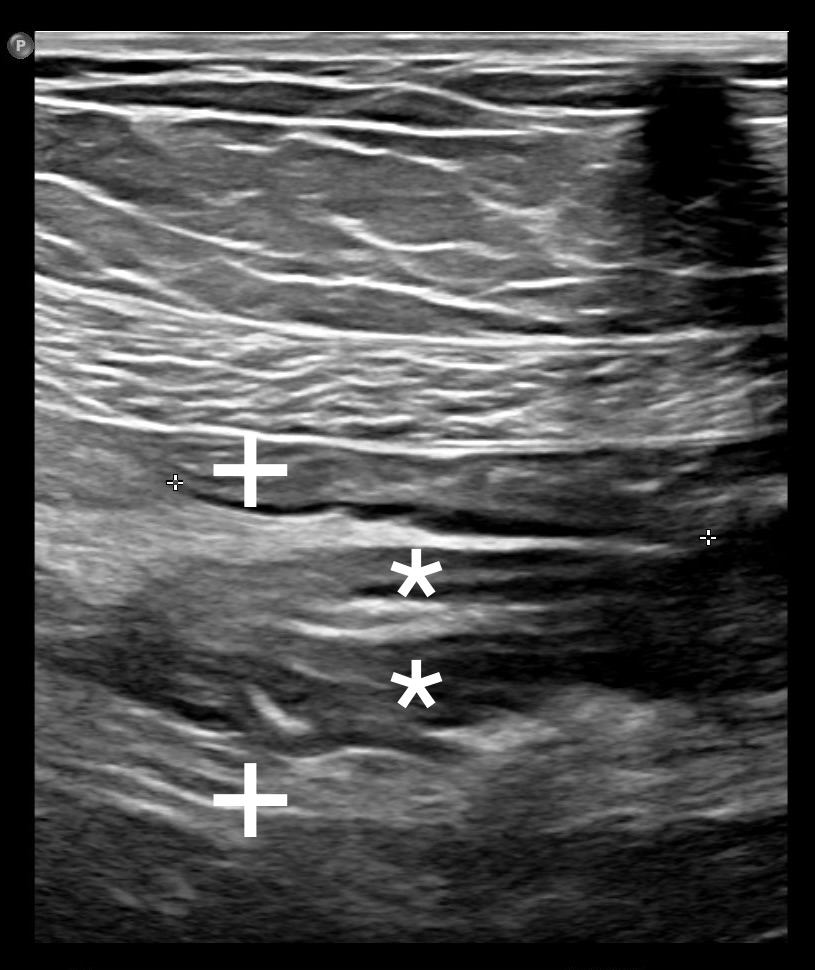

Intussusception of the small intestine occurs when one part of the intestine telescopes into another, causing ischemia and obstruction. This condition is rare in adults, with the most common cause being a benign tumor in the intestinal wall. This paper presents a case of ileal intussusception caused by a submucosal lipoma in the form of a polyp. The intussusception resulted in mild discomfort, and the diagnosis was established through ultrasound and computed tomography scans. Surgical treatment was performed, involving laparoscopic reduction of the intussusception, segmental resection of the intestine, and end-to-end anastomosis. The postoperative course was uneventful.